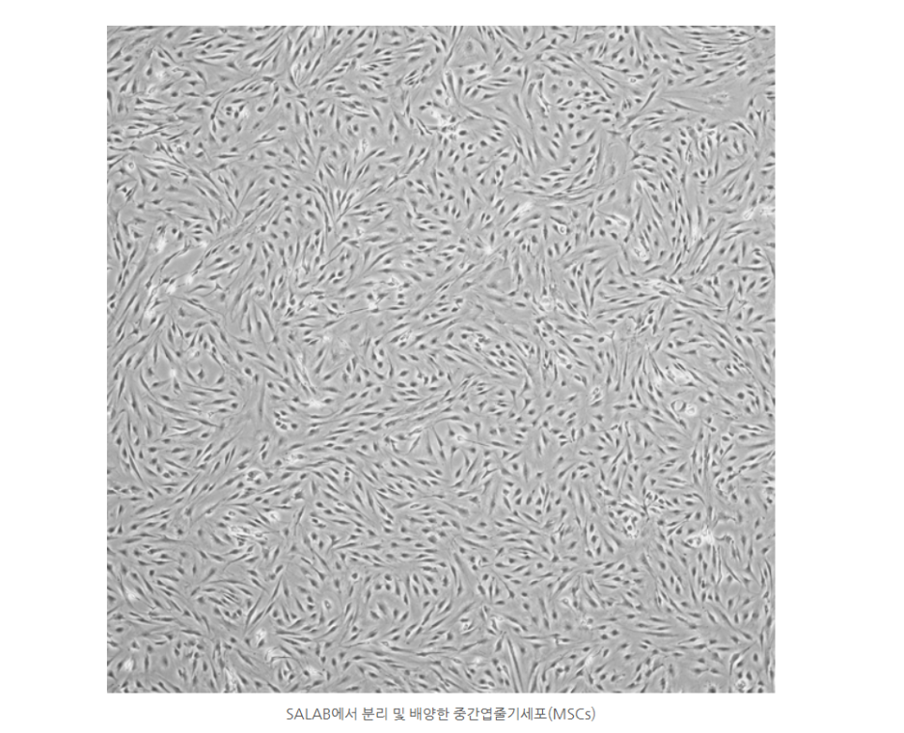

에스동물메디컬센터 양산점은 주로 지방유래 중간엽줄기세포(MSCs, Mesenchymal Stem Cells)가 활용됩니다. 이 세포들은 채취가 용이하고, 면역 조절 및 항염 효과가 뛰어나 반려동물의 만성질환 치료에 많이 응용되고 있습니다.